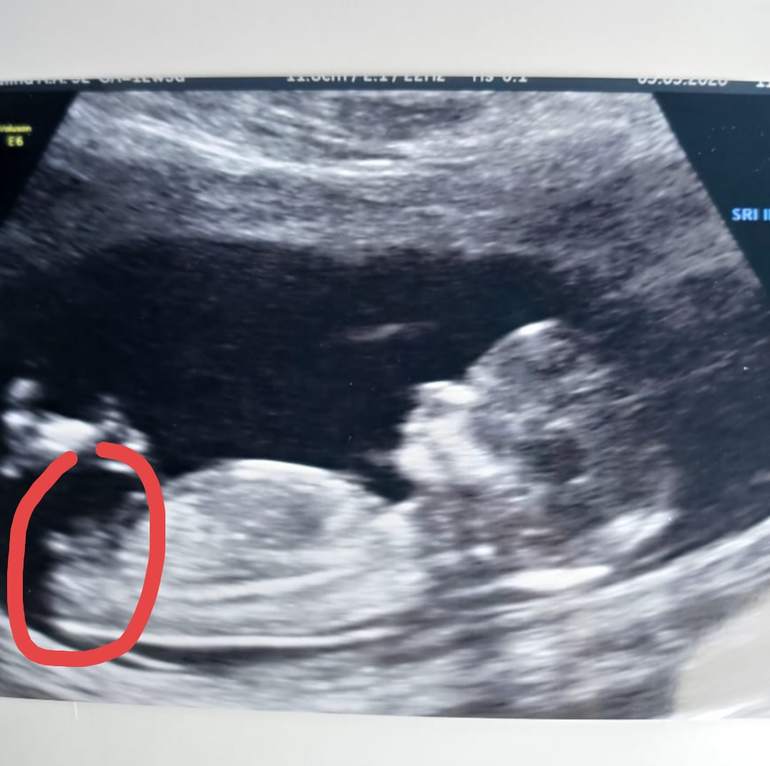

Вот бугорок)

Как я поняла из того, что прочитала - на этом сроке только по положению полового бугорка. У вас на фото он действительно направлен вверх. У меня сейчас я смотрю и тоже теперь понимаю, что параллельно позвоночнику. У вас мальчик, у меня девочка, если все так)

Пол малышаМне сегодня на скрининге предположили пол, но , может тоже посмотрите? Я в этом не разбираюсь совсем, но очень интересно. Если по этому фото можно понять. Врач сказала, что конечно есть шанс на ошибку, но видит девочку. Я очень хочу, чтобы так и было)